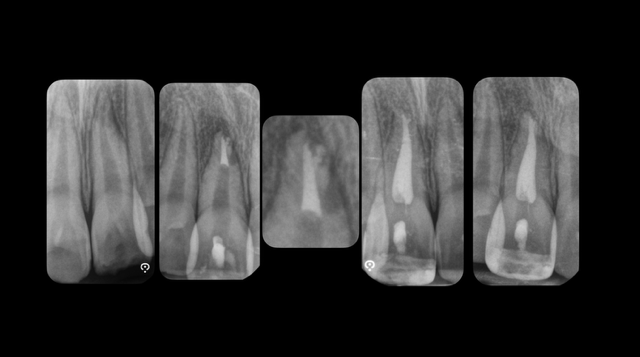

Il ritrattamento endodontico rappresenta una procedura fondamentale per la gestione di denti con fallimento della terapia endodontica primaria. Le cause principali di insuccesso possono essere legate a infezioni persistenti, fratture radicolari, o errori tecnici durante il trattamento iniziale. L’obiettivo del ritrattamento è garantire una completa decontaminazione del sistema canalare, risolvere le infezioni e favorire la guarigione dei tessuti periapicali. Questo intervento, sebbene altamente efficace, comporta sfide tecniche significative, tra cui la difficoltà nell’accesso ai canali radicolari precedentemente trattati, la rimozione di materiali di otturazione, la gestione della curvatura radicolare e la preservazione della struttura dentale residua. L’utilizzo di tecnologie avanzate, come la microscopia operativa, i laser e le apparecchiature per la localizzazione dei canali, ha migliorato notevolmente la precisione e l’efficacia di queste procedure. Durante la relazione verranno discussi i criteri di selezione dei casi da sottoporre a ritrattamento, le tecniche moderne per il trattamento delle infezioni persistenti e le prospettive future in termini di materiali e approcci terapeutici. Sarà inoltre esplorato l’importante ruolo della diagnosi clinica e radiografica per determinare il successo del ritrattamento, così come le implicazioni per la prognosi a lungo termine del dente ritrattato endodonticamente. Il ritrattamento endodontico, pur essendo una procedura complessa, offre una valida soluzione per il salvataggio dei denti compromessi, con ottimi tassi di successo quando eseguito da professionisti esperti e con tecnologie all’avanguardia.